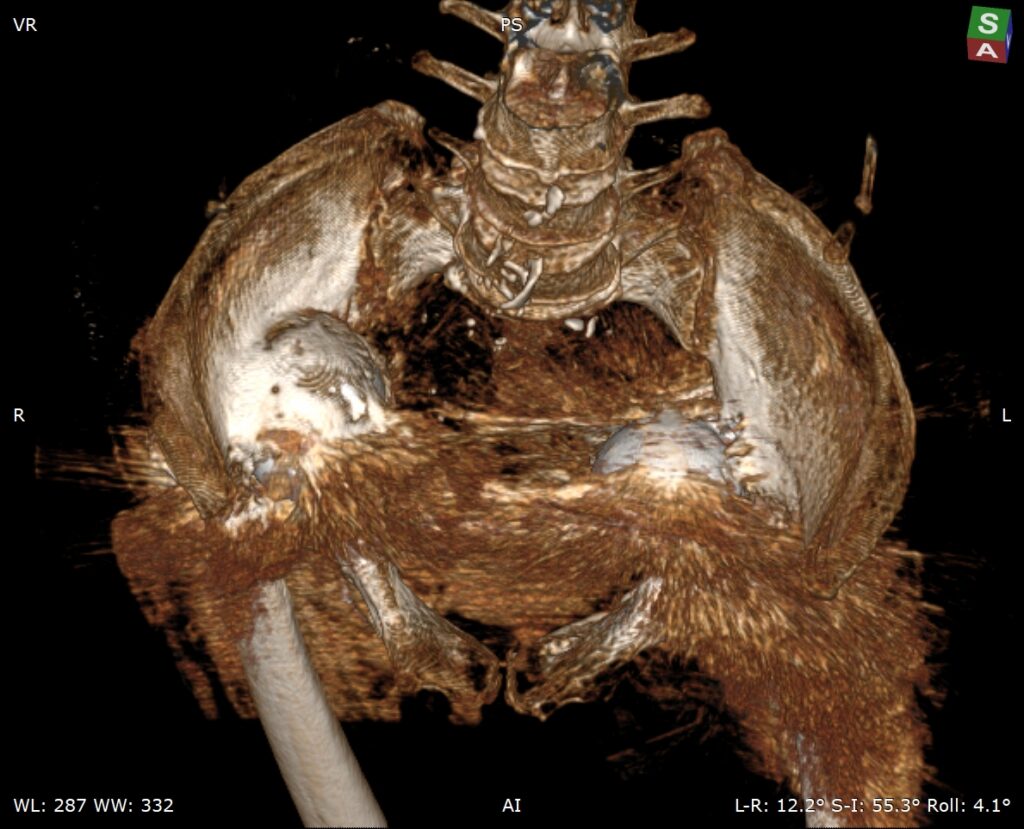

患者老年女性,类风湿性关节炎,骨质疏松,双侧全髋术后,髋臼假体移位至盆腔多年,不能行走。(The patient is an elderly female with rheumatoid arthritis and osteoporosis. After bilateral total hip surgery, the acetabular prosthesis has been displaced into the pelvic cavity for many years and she is unable to walk.)